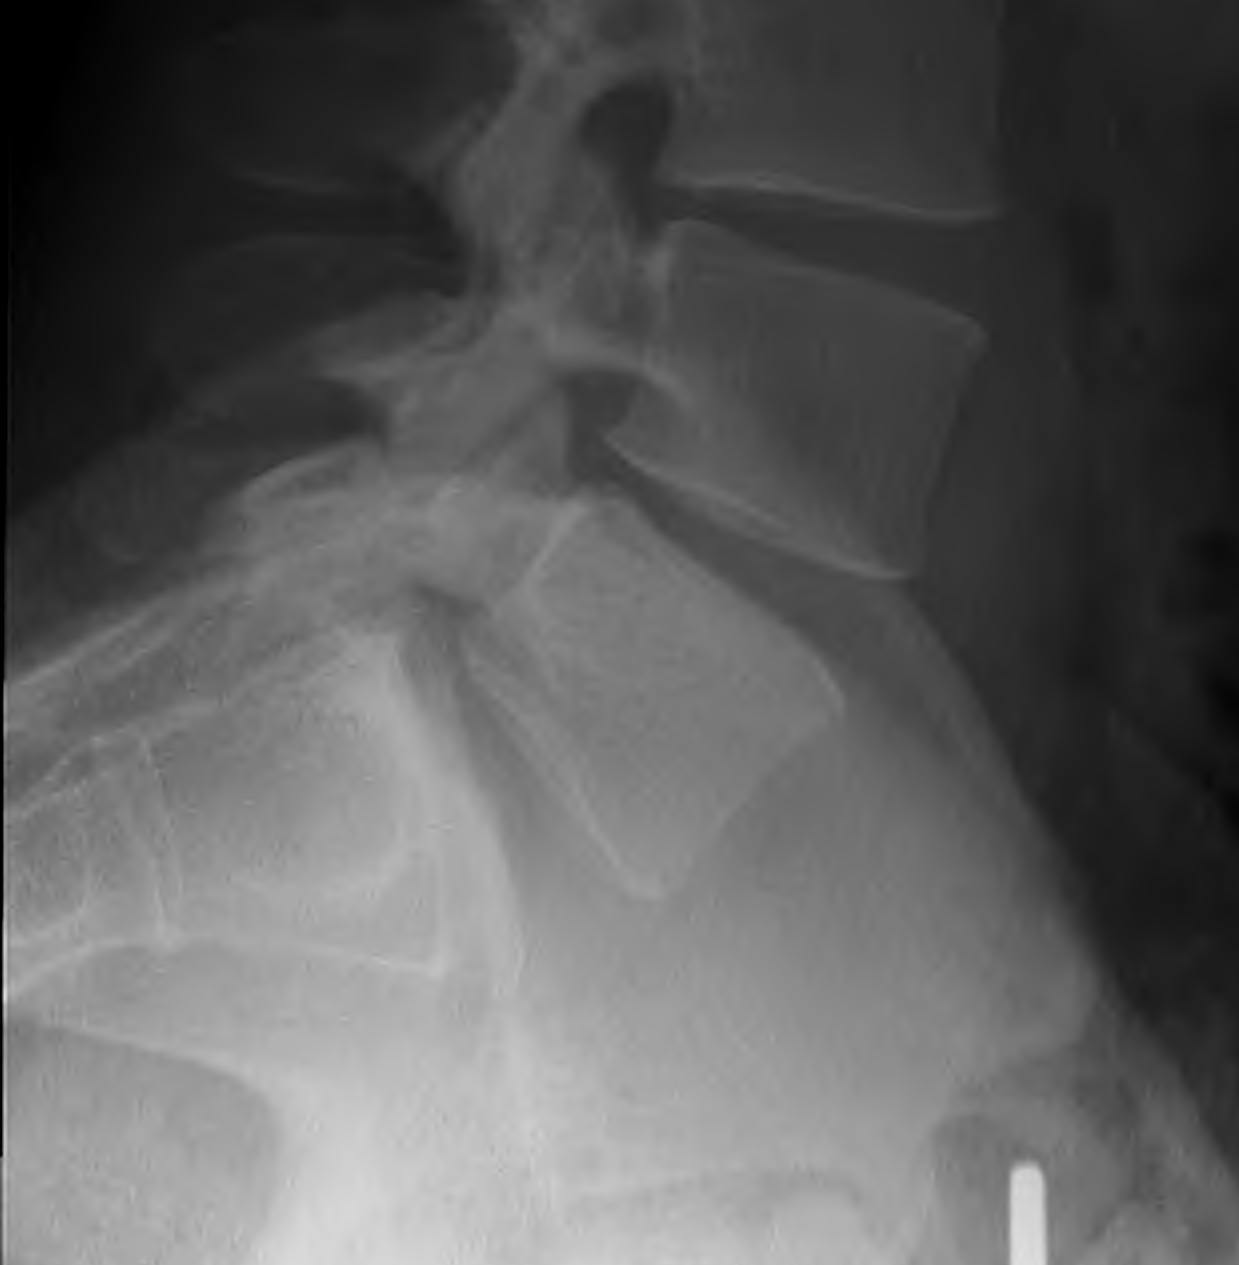

Slip Angle / kyphotic angle

Measurement

- line along inferior border L5

- line along superior border S1

Normally L5/S1 disc is in 20-30° lordosis

- angle is negative

As L5 slips forward it slips into kyphosis

- angle becomes positive

- sacrum becomes more vertical with high grade slips

- this worsens the kyphosis further

Dangers

- typically > 10° with dysplastic

- > 30° high risk progression progression

Sacral inclination

Angle between posterior border of sacrum and vertical

- > 60o associated with progression

Chronic Changes

Seen in older presentation

- anterior sacral erosion

- domed sacrum

- L5 Trapezoidal

- L5/S1 disc degeneration